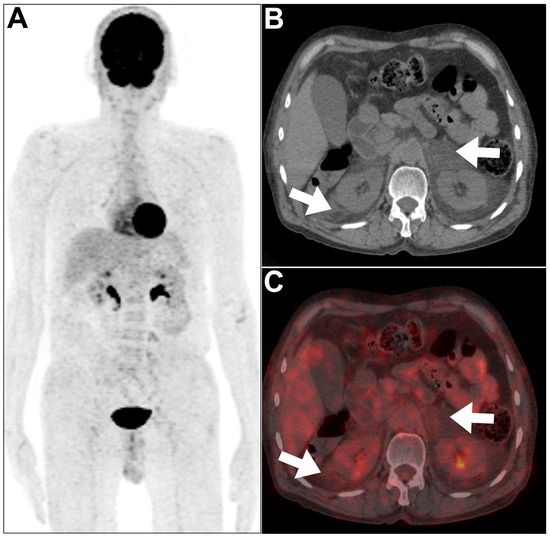

- Pijl, J.P.; Glaudemans, A.W.; Slart, R.H.; Kwee, T.C. 18F-FDG PET/CT in autosomal dominant polycystic kidney disease patients with suspected cyst infection. J. Nucl. Med. 2018, 59, 1734–1741. [Google Scholar] [CrossRef]

- Ronsin, C.; Bailly, C.; Le Turnier, P.; Ville, S. Value of FDG-PET/CT in monitoring cyst infections in patients with autosomal dominant polycystic renal disease. Clin. Kidney J. 2021, 14, 2273–2275. [Google Scholar] [CrossRef]

- Bobot, M.; Ghez, C.; Gondouin, B.; Sallée, M.; Fournier, P.-E.; Burtey, S.; Legris, T.; Dussol, B.; Berland, Y.; Souteyrand, P. Diagnostic performance of [18F] fluorodeoxyglucose positron emission tomography–computed tomography in cyst infection in patients with autosomal dominant polycystic kidney disease. Clin. Microbiol. Infect. 2016, 22, 71–77. [Google Scholar] [CrossRef]